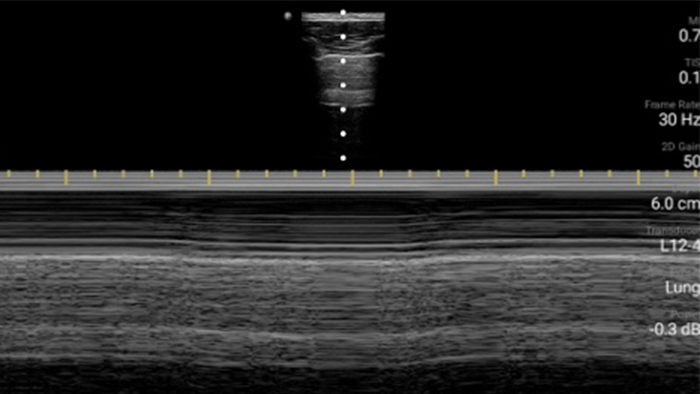

Exceptional ultrasound imaging

Lumify handheld ultrasound offers images that enhance diagnostic confidence.